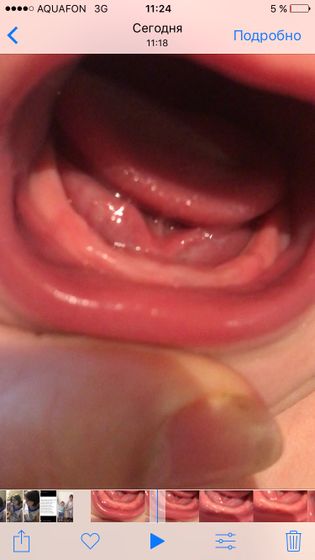

Вторую ночь плохо спим, капризничаем, носик течет, расстройство животика, вроде смотрю, но нечего похожее на зубики не вижу. Здесь же много опытных мамочек, подскажите пожалуйста что это может быть.

Скоро прорежутся судя по фото

Я тоже не вижу, но они ведь изнутри так лезут, что может быть не видно

По мне так они даже не опухшие, десна.